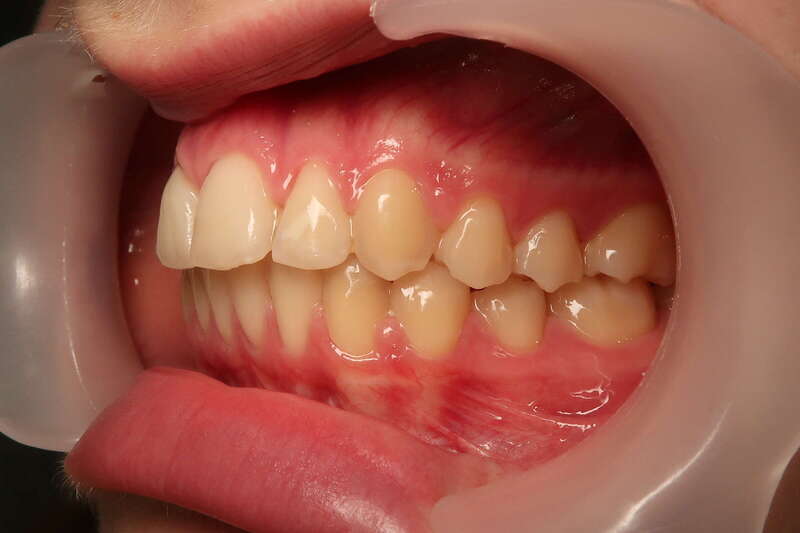

Cas n°1 traité par aligneurs - adolescent

Ce cas d’une adolescente illustre la correction d'une Classe II avec supraclusion par aligneurs. La stratégie thérapeutique a reposé sur une distalisation séquentielle de l'arcade supérieure. Ce mouvement précis a permis de reculer les dents maxillaires étape par étape pour annuler le surplomb (overjet) sans extractions.

• Correction fonctionnelle : Retour à un engrènement de Classe I stable et correction du recouvrement vertical.

• Esthétique restaurée : Harmonisation globale du sourire et du profil.

• Approche moderne : Un traitement discret, confortable et hautement prévisible.

Le résultat final montre une occlusion saine et un sourire parfaitement aligné, garantissant une santé dentaire et articulaire optimale pour l'avenir.